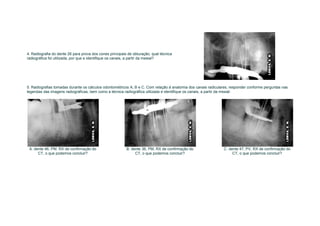

4. Radiografia do dente 26 para prova dos cones principais de obturação, qual técnica

radiográfica foi utilizada, por que e identifique os canais, a partir da mesial?

5. Radiografias tomadas durante os cálculos odontométricos A, B e C. Com relação à anatomia dos canais radiculares, responder conforme perguntas nas

legendas das imagens radiográficas, bem como a técnica radiográfica utilizada e identifique os canais, a partir da mesial:

A. dente 46, PM, RX de confirmação do                    B. dente 36, PM, RX de confirmação do                C. dente 47, PV, RX de confirmação do

CT, o que podemos concluir?                              CT, o que podemos concluir?                          CT, o que podemos concluir?